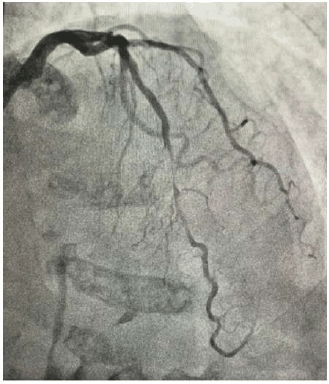

Mulher de 62 anos é diabética e hipertensa, com quadro de angina rapidamente progressiva, atualmente aos mínimos esforços. Foi solicitada uma cinecoronariografia, que está reproduzida abaixo.

Ao interpretar o exame, o cardiologista conclui tratar-se de